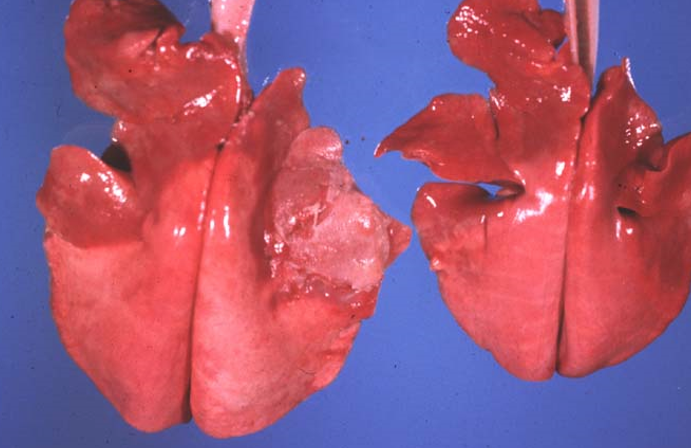

Καρδιά χοίρου

Ανθοκραμβοειδείς εκβλαστήσεις στο ενδοκάρδιο (χρόνια υπερπλαστική ενδοκαρδίτιδα) λόγω ερυθράς του χοίρου. Από Erisypelotrix

Διόγκωση της δεξιάς καρδιάς στο σκύλο. Διατατική μυοκαρδιοπάθεια